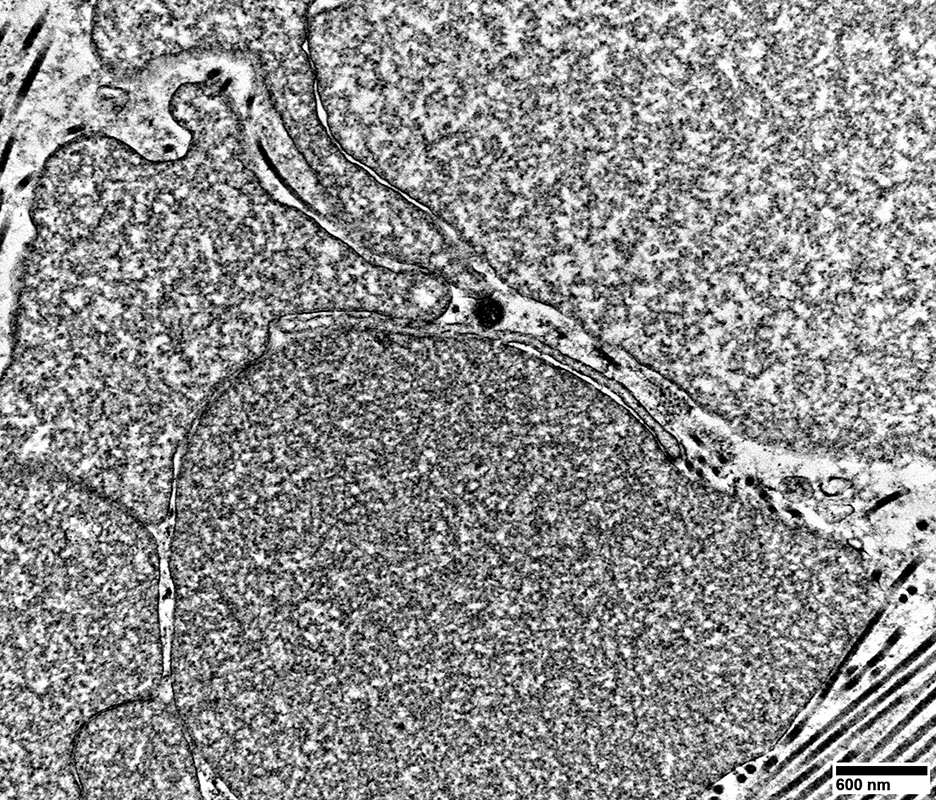

Regenerating Axons

Cluster of moderate-sized processes

All contain mainly Tubulovesicular profiles

Densely distributed

No surrounding Schwann cell cytoplasm

From: R Schmidt